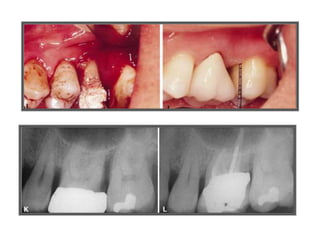

TRATAMENTO DAS LESÕES

ENDOPERIODONTAIS

Rizectomia

DEL RIO, 1996

Rizectomia

Hemisseccção